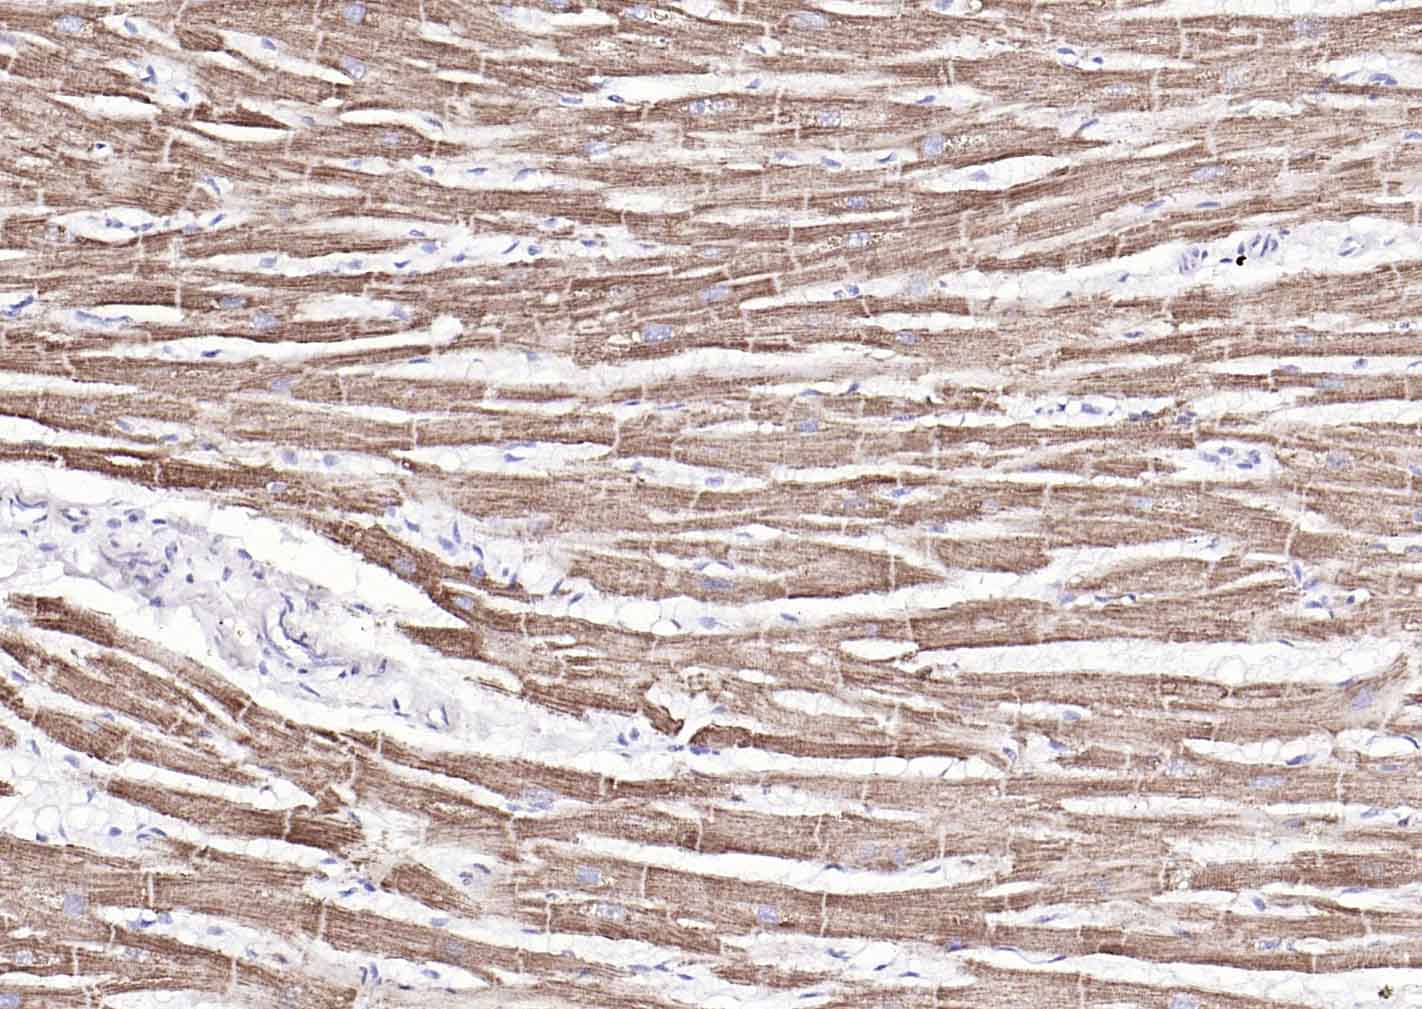

Paraformaldehyde-fixed, paraffin embedded (human heart); Antigen retrieval by boiling in sodium citrate buffer (pH6.0) for 15min; Block endogenous peroxidase by 3% hydrogen peroxide for 20 minutes; Blocking buffer (normal goat serum) at 37°C for 30min; Incubation with (COX4I1(Mitochondrial Loading Control)) Monoclonal Antibody, Unconjugated (bsm-33037M) at 1:100 overnight at 4°C, followed by operating according to SP Kit(Mouse)(sp-0024) instructionsand DAB staining.

Paraformaldehyde-fixed, paraffin embedded (Rat skeletal muscle); Antigen retrieval by boiling in sodium citrate buffer (pH6.0) for 15min; Block endogenous peroxidase by 3% hydrogen peroxide for 20 minutes; Blocking buffer (normal goat serum) at 37°C for 30min; Antibody incubation with (COX4) Monoclonal Antibody, Unconjugated (bsm-33037M) at 1:400 overnight at 4°C, followed by a conjugated secondary (sp-0023) for 20 minutes and DAB staining.

Paraformaldehyde-fixed, paraffin embedded (rat heart); Antigen retrieval by boiling in sodium citrate buffer (pH6.0) for 15min; Block endogenous peroxidase by 3% hydrogen peroxide for 20 minutes; Blocking buffer (normal goat serum) at 37°C for 30min; Incubation with (COX4I1(Mitochondrial Loading Control)) Monoclonal Antibody, Unconjugated (bsm-33037M) at 1:100 overnight at 4°C, followed by operating according to SP Kit(Mouse)(sp-0024) instructionsand DAB staining.

Paraformaldehyde-fixed, paraffin embedded (mouse heart); Antigen retrieval by boiling in sodium citrate buffer (pH6.0) for 15min; Block endogenous peroxidase by 3% hydrogen peroxide for 20 minutes; Blocking buffer (normal goat serum) at 37°C for 30min; Incubation with (COX4I1(Mitochondrial Loading Control)) Monoclonal Antibody, Unconjugated (bsm-33037M) at 1:100 overnight at 4°C, followed by operating according to SP Kit(Mouse)(sp-0024) instructionsand DAB staining.

Paraformaldehyde-fixed, paraffin embedded (Human heart); Antigen retrieval by boiling in sodium citrate buffer (pH6.0) for 15min; Block endogenous peroxidase by 3% hydrogen peroxide for 20 minutes; Blocking buffer (normal goat serum) at 37°C for 30min; Incubation with (COX4I1(Mitochondrial Loading Control) ) Monoclonal Antibody, Unconjugated (bsm-33037M) at 1:200 overnight at 4°C, followed by operating according to SP Kit(Mouse)(sp-0024) instructionsand DAB staining.

Paraformaldehyde-fixed, paraffin embedded (Rat skeletal muscle); Antigen retrieval by boiling in sodium citrate buffer (pH6.0) for 15min; Block endogenous peroxidase by 3% hydrogen peroxide for 20 minutes; Blocking buffer (normal goat serum) at 37°C for 30min; Antibody incubation with (COX4) Monoclonal Antibody, Unconjugated (bsm-33037M-8D8) at 1:500 overnight at 4°C, followed by a conjugated secondary (sp-0023) for 20 minutes and DAB staining.